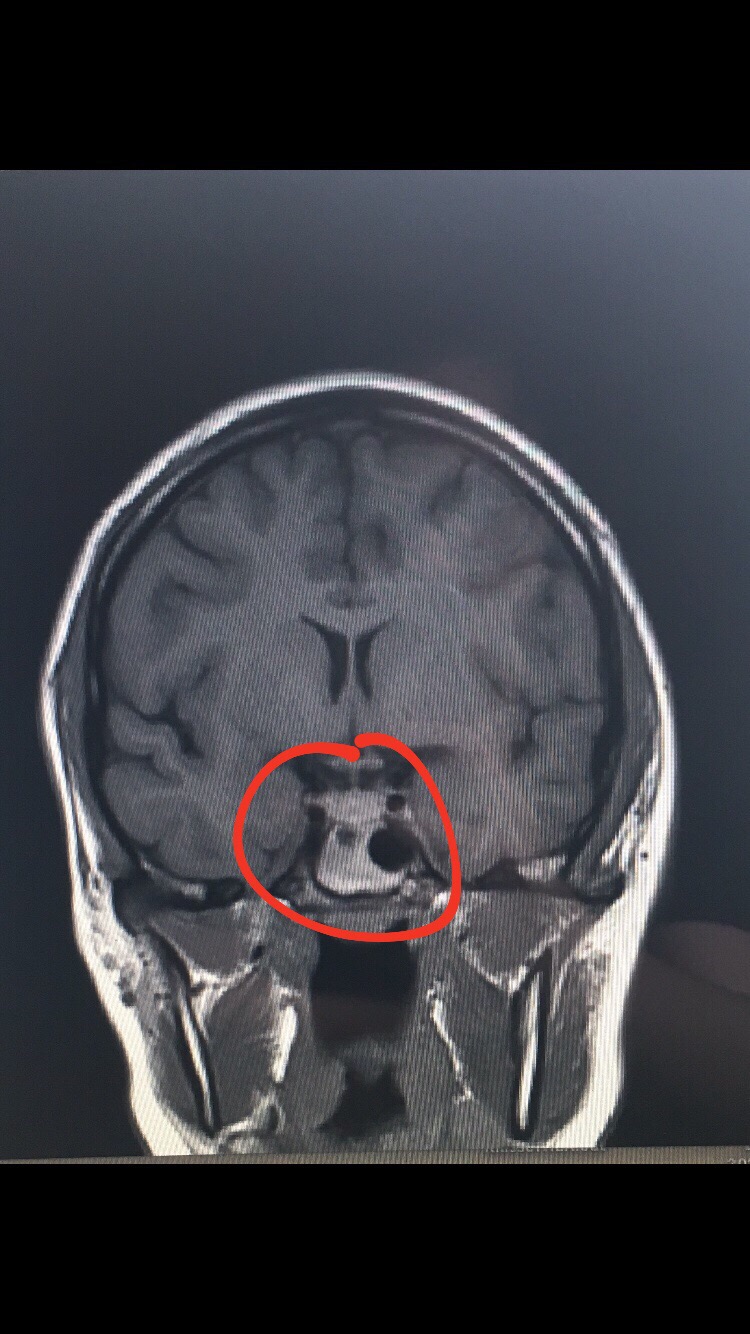

Abb 2 Links Koronarer Schnitt durch den Schädel (MRT, T1Wichtung) in Höhe der Kranznaht Eine Ventrikelpunktion ist bei klinischen Zeichen einer Liquorzirkulationsstörung und dem bildmorphologischen Nachweis einer entsprechenden Veränderung in der Computer oder Kernspintomographie indiziert. Bertrand Daniel A E Schädel, Origenes, Die griechisch erhaltenen Jeremiahomilien, Stuttgart, Anton Hiersemann, 1980 (Bibliothek der griechischen Literatur 10) In Revue d'histoire et de philosophie religieuses, 62e année n°3, Juilletseptembre 19 p 284. Die abgebildeten MRTBilder zeigen eine abgeschwächte Signalgebung im T2gewichteten Bild und eine intermediäre Signalgebung im T1gewichteten Bild (gelbe Pfeile) Diese Befunde sind mit einer akuten Blutung in Einklang zu bringen Mit zunehmendem Zeitabstand fängt Blut an, seine Eigenschaften hinsichtlich der Signalgebung zu verändern.

Abb 2 Links Koronarer Schnitt durch den Schädel (MRT, T1Wichtung) in Höhe der Kranznaht Eine Ventrikelpunktion ist bei klinischen Zeichen einer Liquorzirkulationsstörung und dem bildmorphologischen Nachweis einer entsprechenden Veränderung in der Computer oder Kernspintomographie indiziert. MRT 2 betrachten MRT 2 Schädel Coronaransicht (T2Wichtung) MRT 3 betrachten MRT 3 (FLAIR)Raumforderung links occipital signalreich MRT 4 betrachten MRT 4 (T1Wichtung)hypointense Raumforderung links occipital MRT 5 betrachten MRT 5 Transversalansicht (T1Wichtung nach KM iv)kein pathologisches Enhancement in der Raumforderung. Bild 30 GehirnMRT sagittale Schnitt, T1gewichteten 1, untere Schläfenwindung (Gyrus temporalis inferior) 2, mittlere Schläfenwindung (Gyrus temporalis medius) 3, obere Schläfenwindung (Gyrus temporalis superior) 4, Zentralfurche (Sulcus centralis) 5, Kleinhirn (Cerebellum).